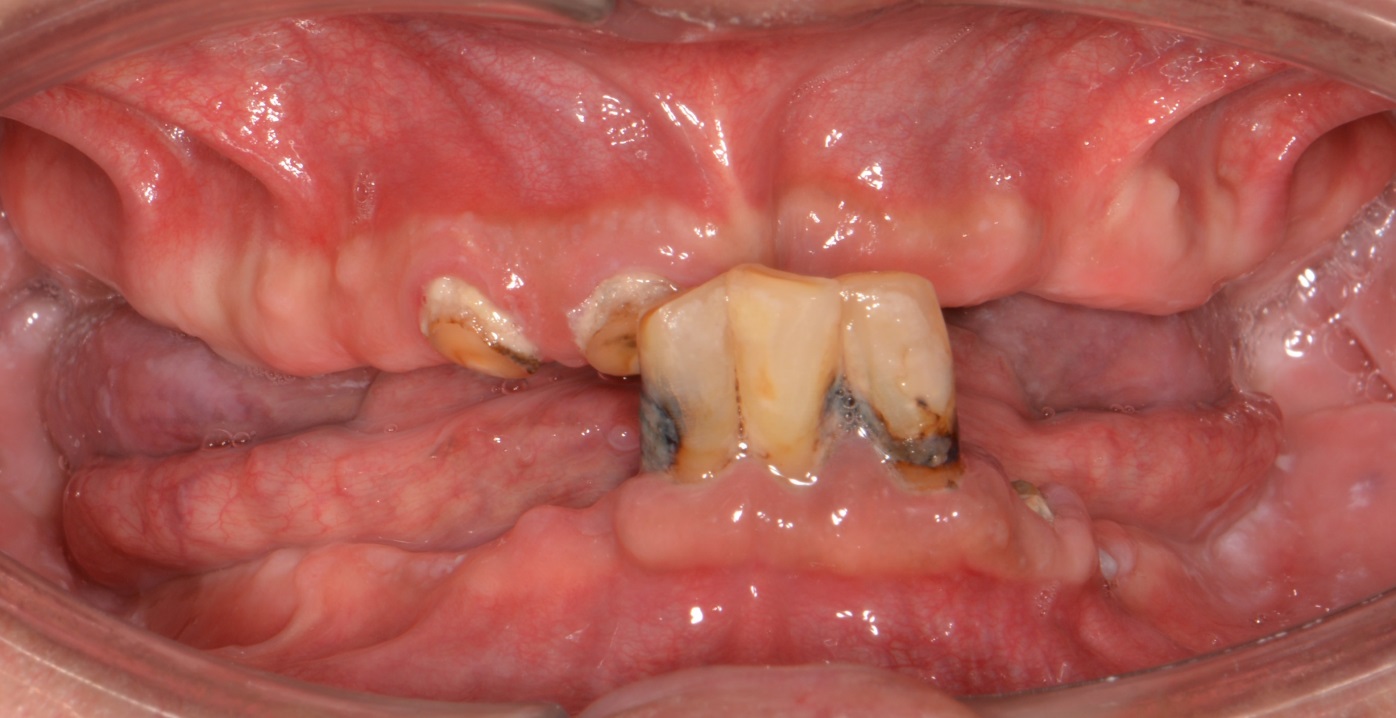

상,하악 완전틀니

Before

안 좋은 치아를 모두 발치하고,

상,하악 모두 완전 틀니로 진행하였습니다.